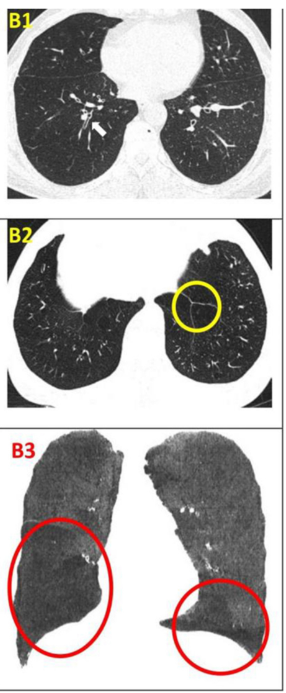

影像學檢查:對于患者 #2902,定量分析顯示基線時總體肺氣腫面積比為 12.75%,移植后 24 周降至 10.02%。在患者 #8009 中,肺氣腫面積比值從基線的 10.85% 下降到移植后 12 周的 9.08%。CT 圖像的三維可視化顯示,肺氣腫的減輕在下葉比在上葉更明顯。

影像學檢查:隨訪12個月時,定量胸部CT掃描示患者吸入總肺容積略有增加,肺氣腫指數無明顯變化。支氣管壁厚度(WT)的變化以WT、壁面積(WA)及WA百分比(%WA)的減少,以及支氣管內徑(ID)和管腔面積(LA)的增大來評估。

干細胞治療一年后,雙肺RB1和RB10的WT均減少,LA增加(粗體指數)。